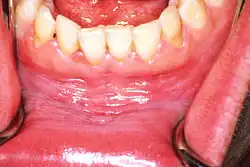

Leukoplakia in the lower labial sulcus

Sometimes leukoplakia of the floor of mouth or under the tongue is called sublingual keratosis,.[19] though this is not universally accepted to be a distinct clinical entity from idiopathic leukoplakia generally,[19] as it is distinguished from the latter by location only.[3] Usually sublingual keratoses are bilateral and possess a parallel-corrugated, wrinkled surface texture described as "ebbing tide".[3]